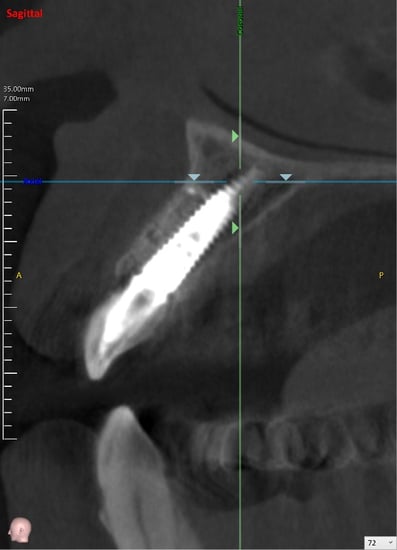

抜歯した直後にインプラントを埋入し、仮の歯を作製、唇側の骨のボリュームを保つために人工骨と結合組織を同時に移植する非常に優れた方法です。

既存の骨の形態分類(ClassⅠ〜Ⅳ)のClassⅢまでは埋入可能とされています。